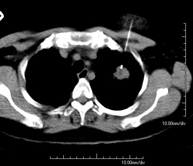

- TC Tórax

Prueba diagnóstica que consiste en obtener imágenes del tórax de alta definición anatómica (pulmones, corazón, mediastino, grandes vasos, caja torácica, etc.) mediante el empleo de un equipo de TC (Tomografía Computarizada). Dichas imágenes se estudian posteriormente en una estación de trabajo que permite reconstrucciones bidimendionales en diferentes planos del espacio y también reconstrucciones 3D (volumétricas). Algunos estudios requieren el empleo de contraste yodado para mejorar la definición de las imágenes. - Angio-TC Aorta torácica

Prueba radiológica que consiste en obtener imágenes del cuello de alta definición anatómica mediante el empleo de un equipo de TC (Tomografía Computarizada). Indicaciones: infecciones, abscesos, estudio ganglios. - TC Tórax

Prueba diagnóstica que consiste en obtener imágenes del tórax de alta definición anatómica (pulmones, corazón, mediastino, grades vasos, caja torácica, etc.) mediante el empleo de un equipo de TC (Tomografía Computarizada). Dichas imágenes se estudian posteriormente en una estación de trabajo que permite reconstrucciones bidimendionales en diferentes planos del espacio, y también reconstrucciones tridimensionales (3D: volumétricas). Algunos estudios requieren el empleo de contraste yodado para mejorar la definición de las imágenes. - TC Abdomen